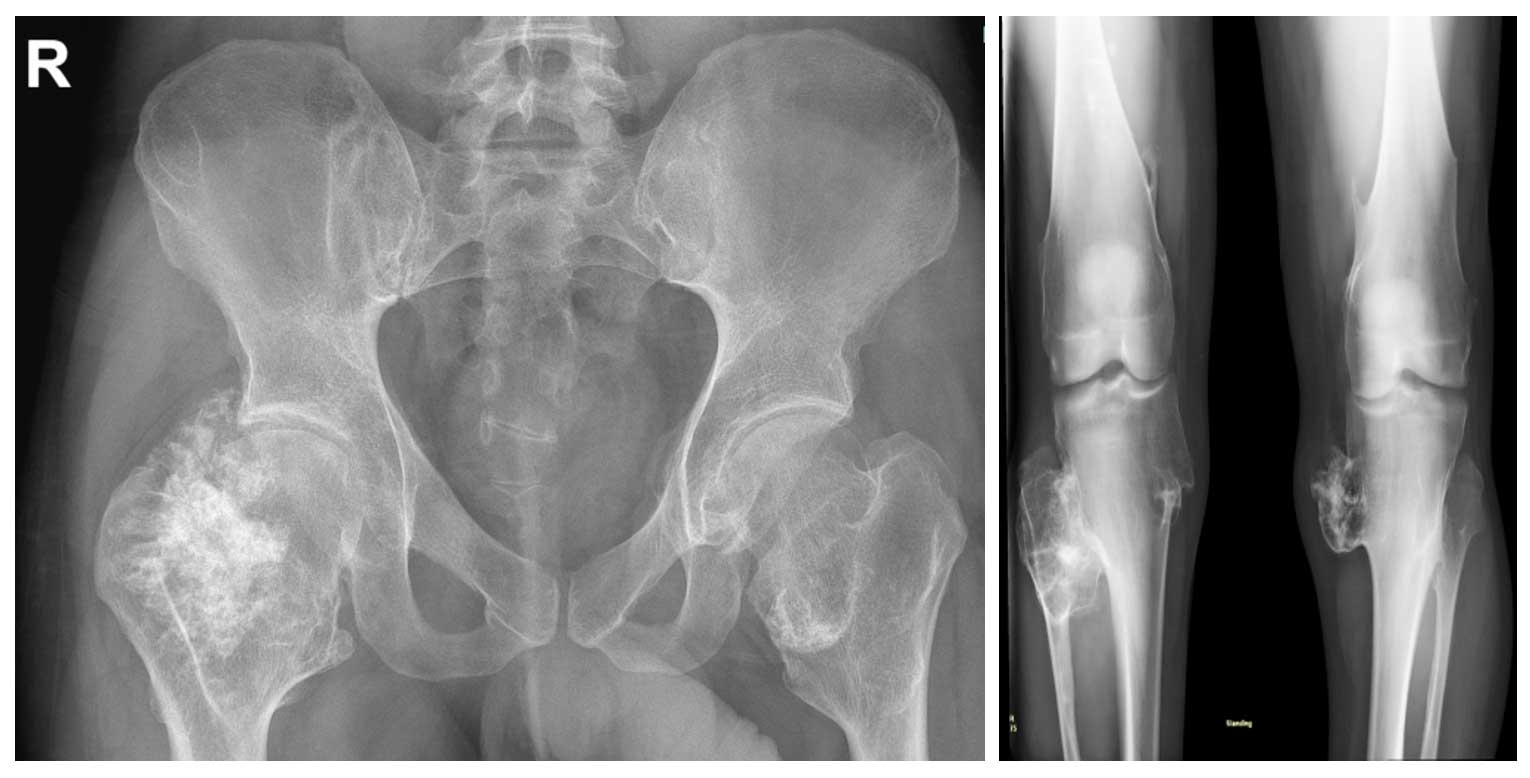

Ameliyat Öncesi: Röntgende kalça ve diz çevresinde yaygın osteokondromlar görülmekte.

Ameliyat Sonrası: Röntgende tümörün çıkarıldığı görülmekte.